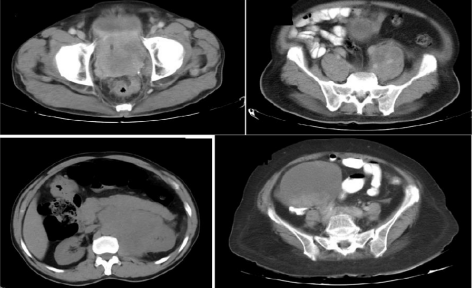

A total of 14 patients with histologically confirmed NEC were available. There were 11 males and 3 females. Out of 11 males, nine had prostatic NEC, one each had adrenal and urachal NEC. Among females (n-3), one each had ovarian, cervix and endometrial NEC. The median age was 70 years (range 59-80 years). The relevant imaging and histopathological images are presented in Fig 1 and Fig 2 respectively. The summary of patient characteristics, their treatment and outcome are summarised in Table 1.

Fig 1(A): Computed Tomography (CT) of the pelvis showing large prostatic mass with infiltration of bladder base and seminal vesicles

Fig 1(B): CT abdomen showing common iliac lymph nodes measuring 6.8 cm, in the patient with prostatic mass.

Fig 1(C): CT abdomen showing left supra renal mass, 57x62x60mm at the level of coeliac origin.

Fig 1(D): CT abdomen/pelvis showing complex right adnexal mass 10.4x10x11cm.